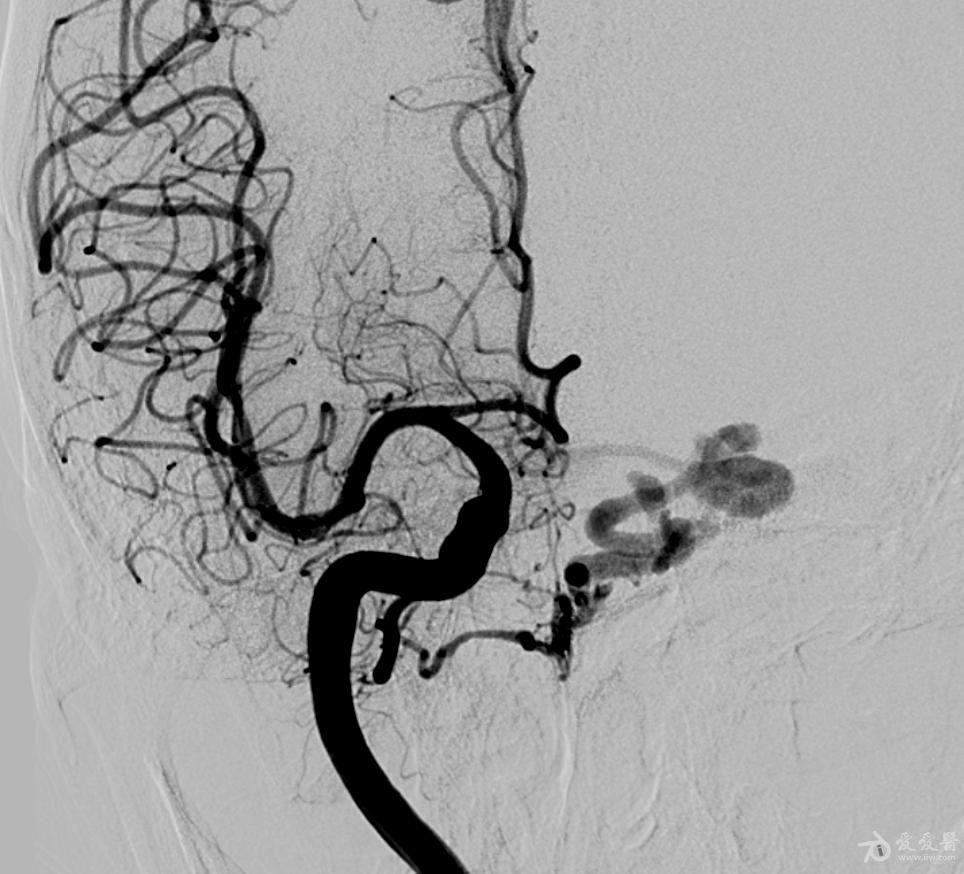

一例硬脑膜动静脉瘘病人介入治疗

齐医附属三院神经外一科成功完成介入微创治疗颅内动脉瘤合并复杂血管

医患沟通 | 脑动静脉瘘,术前可以这样沟通